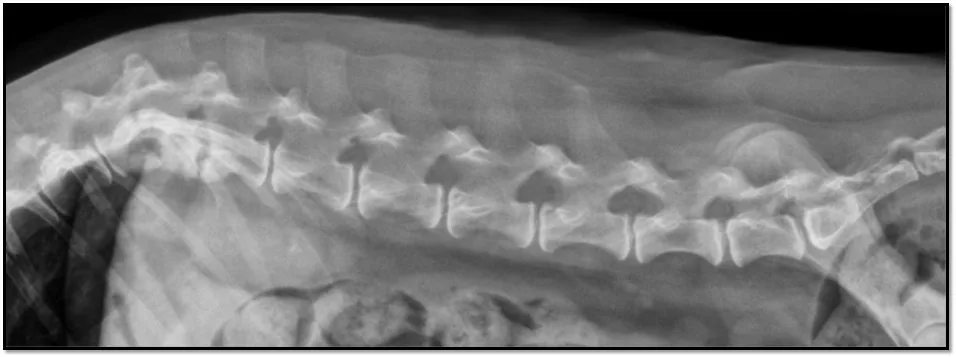

This lateral spinal radiograph highlights classic changes—end plate sclerosis, lysis, and collapse—that point toward discospondylitis and help distinguish infection from degeneration.